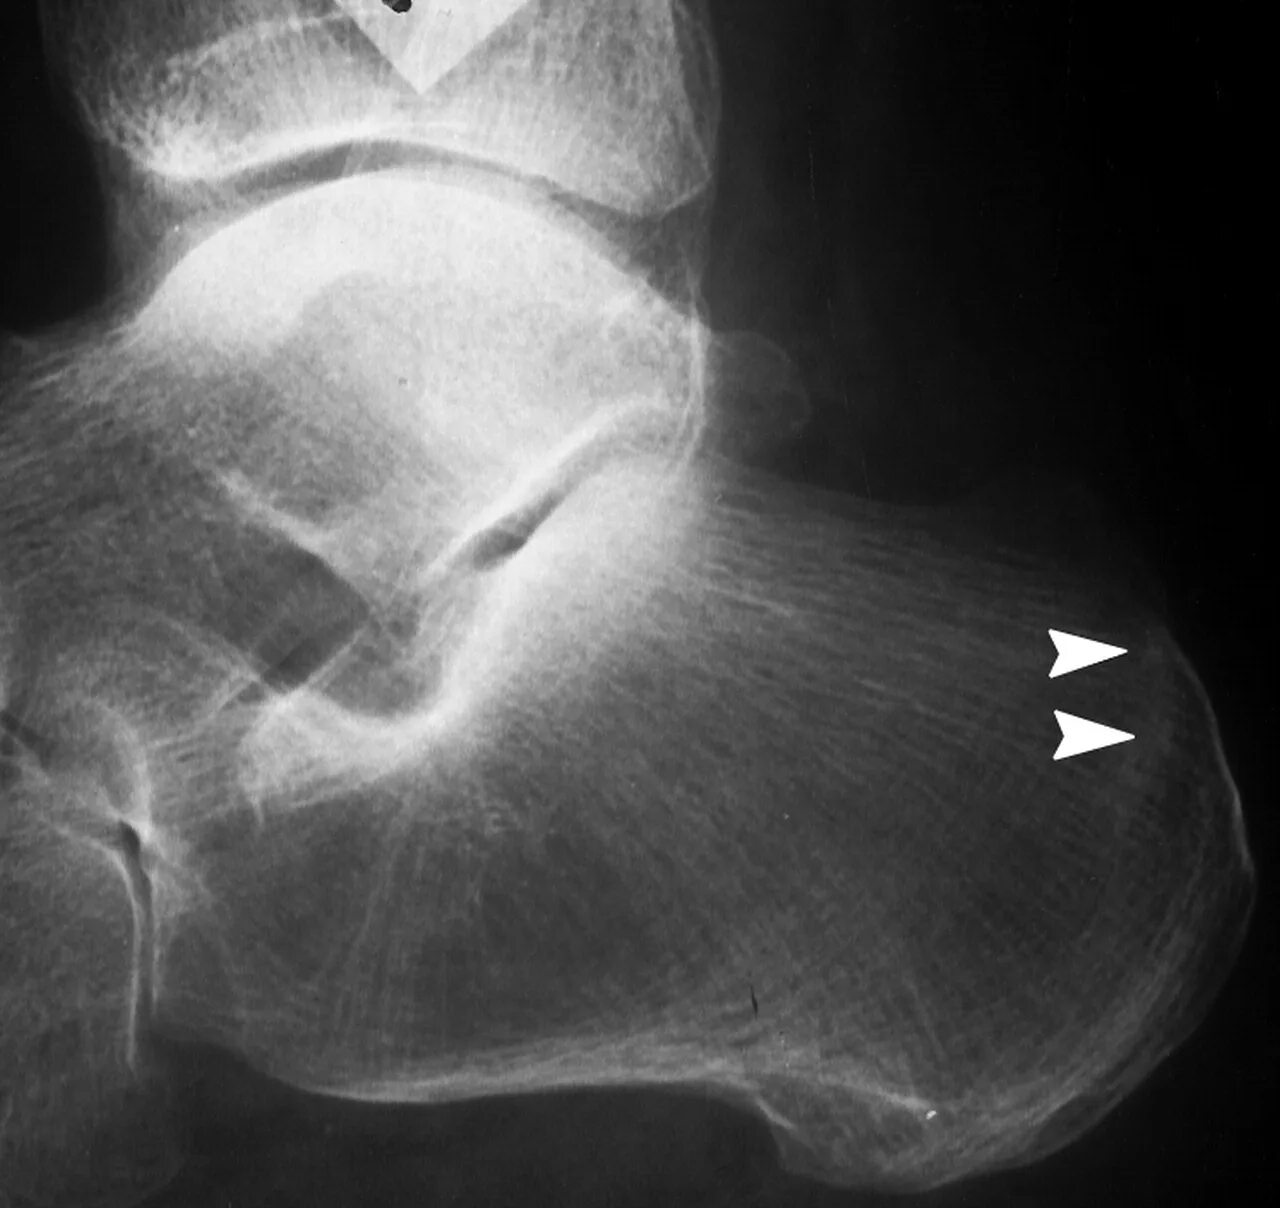

Перелом заднего